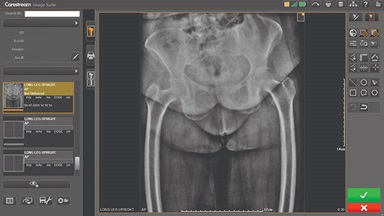

CARESTREAM Image Suite V4 MR11 has set a new standard for workflow efficiency, offering a robust set of features and functionalities to enhance clinical confidence in healthcare professionals. Using an auto-generated companion image from a single exposure, leverage a range of image processing options to increase diagnostic accuracy and enhance patient care.

Our Carestream Focus HD 35/43 Retrofit Detectors, powered by Image Suite Software, are an ideal solution to step up to full digital X-ray for customers who simply cannot compromise on image quality. It seamlessly integrates into existing setups, bringing the power of full digital X-ray with minimal disruption and maximum clarity, along with the following benefits: